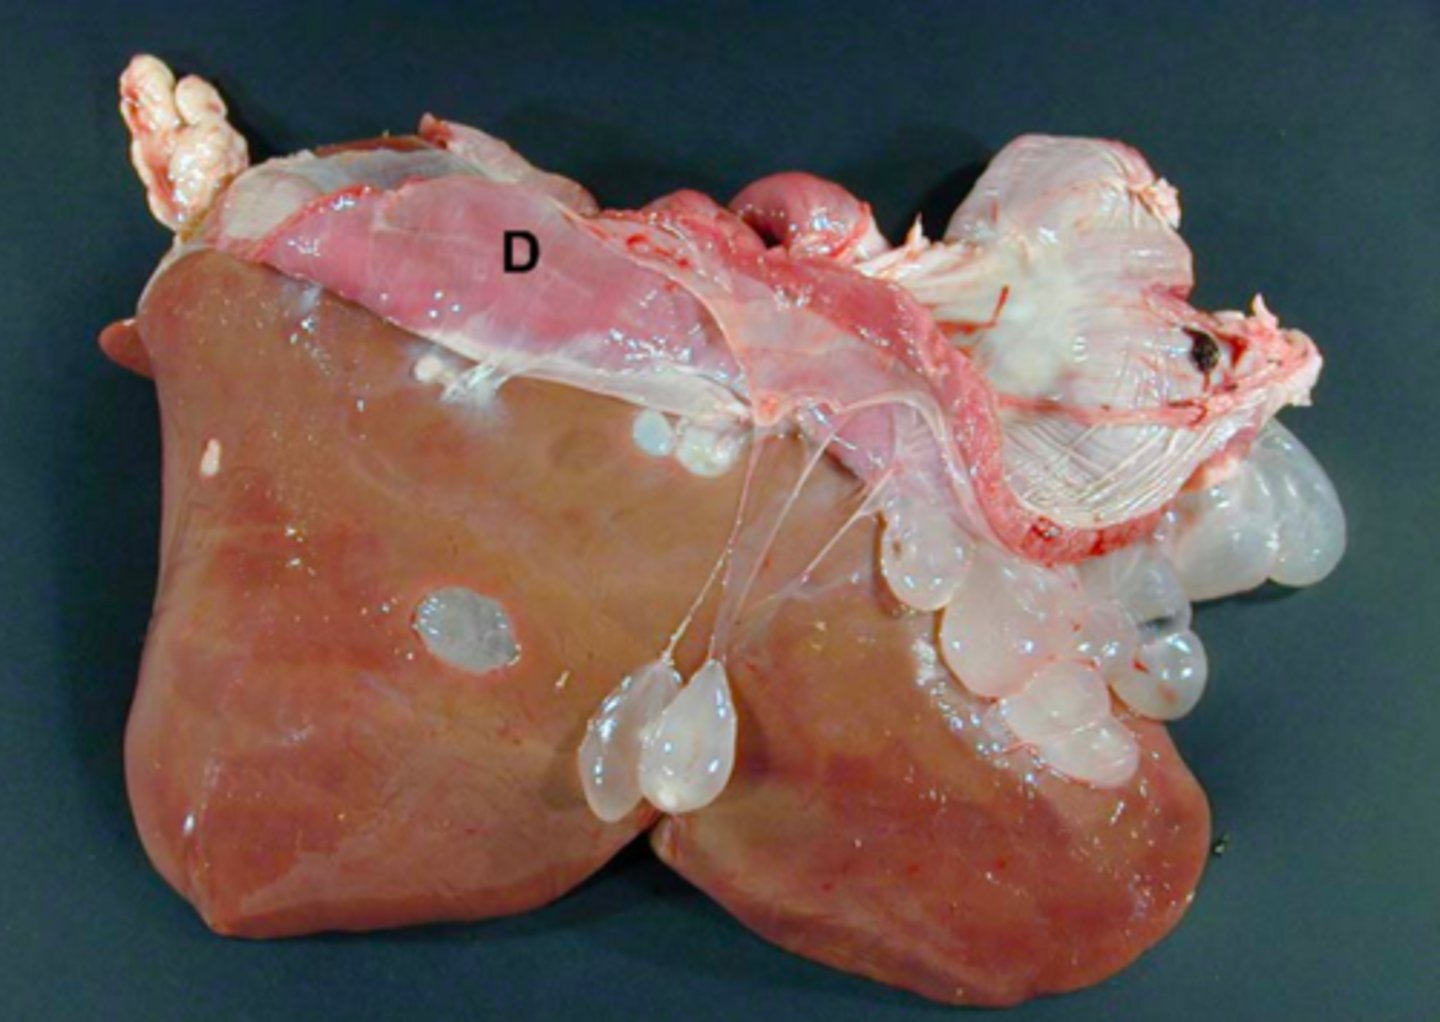

Kronisk peritoneal og perihepatisk cystecerkose

Ætiologi: Cysticerus tenuicollis

Lever fra får (med diaphragma, D), hvad er den patoanatomiske diagnose og ætiologien?